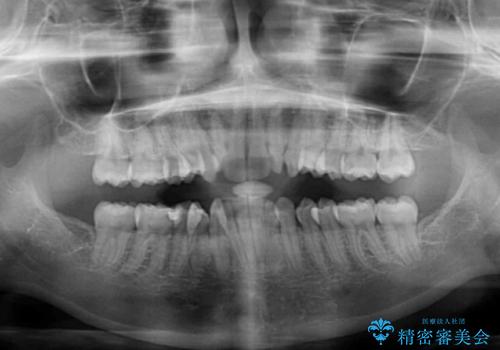

- 上下前歯のデコボコを気にして来院された患者様です。

口元の突出感はあまりなかったものの、デコボコを非抜歯で改善すると出っ歯になる可能性があるため、上下左右の第一小臼歯4本を抜歯し、ワイヤー装置にて矯正治療を行うこととしました。

口元の突出感がない分、奥歯を前方に移動させる必要がありましたが、予定の2年間で無事に治療を終えることができました。